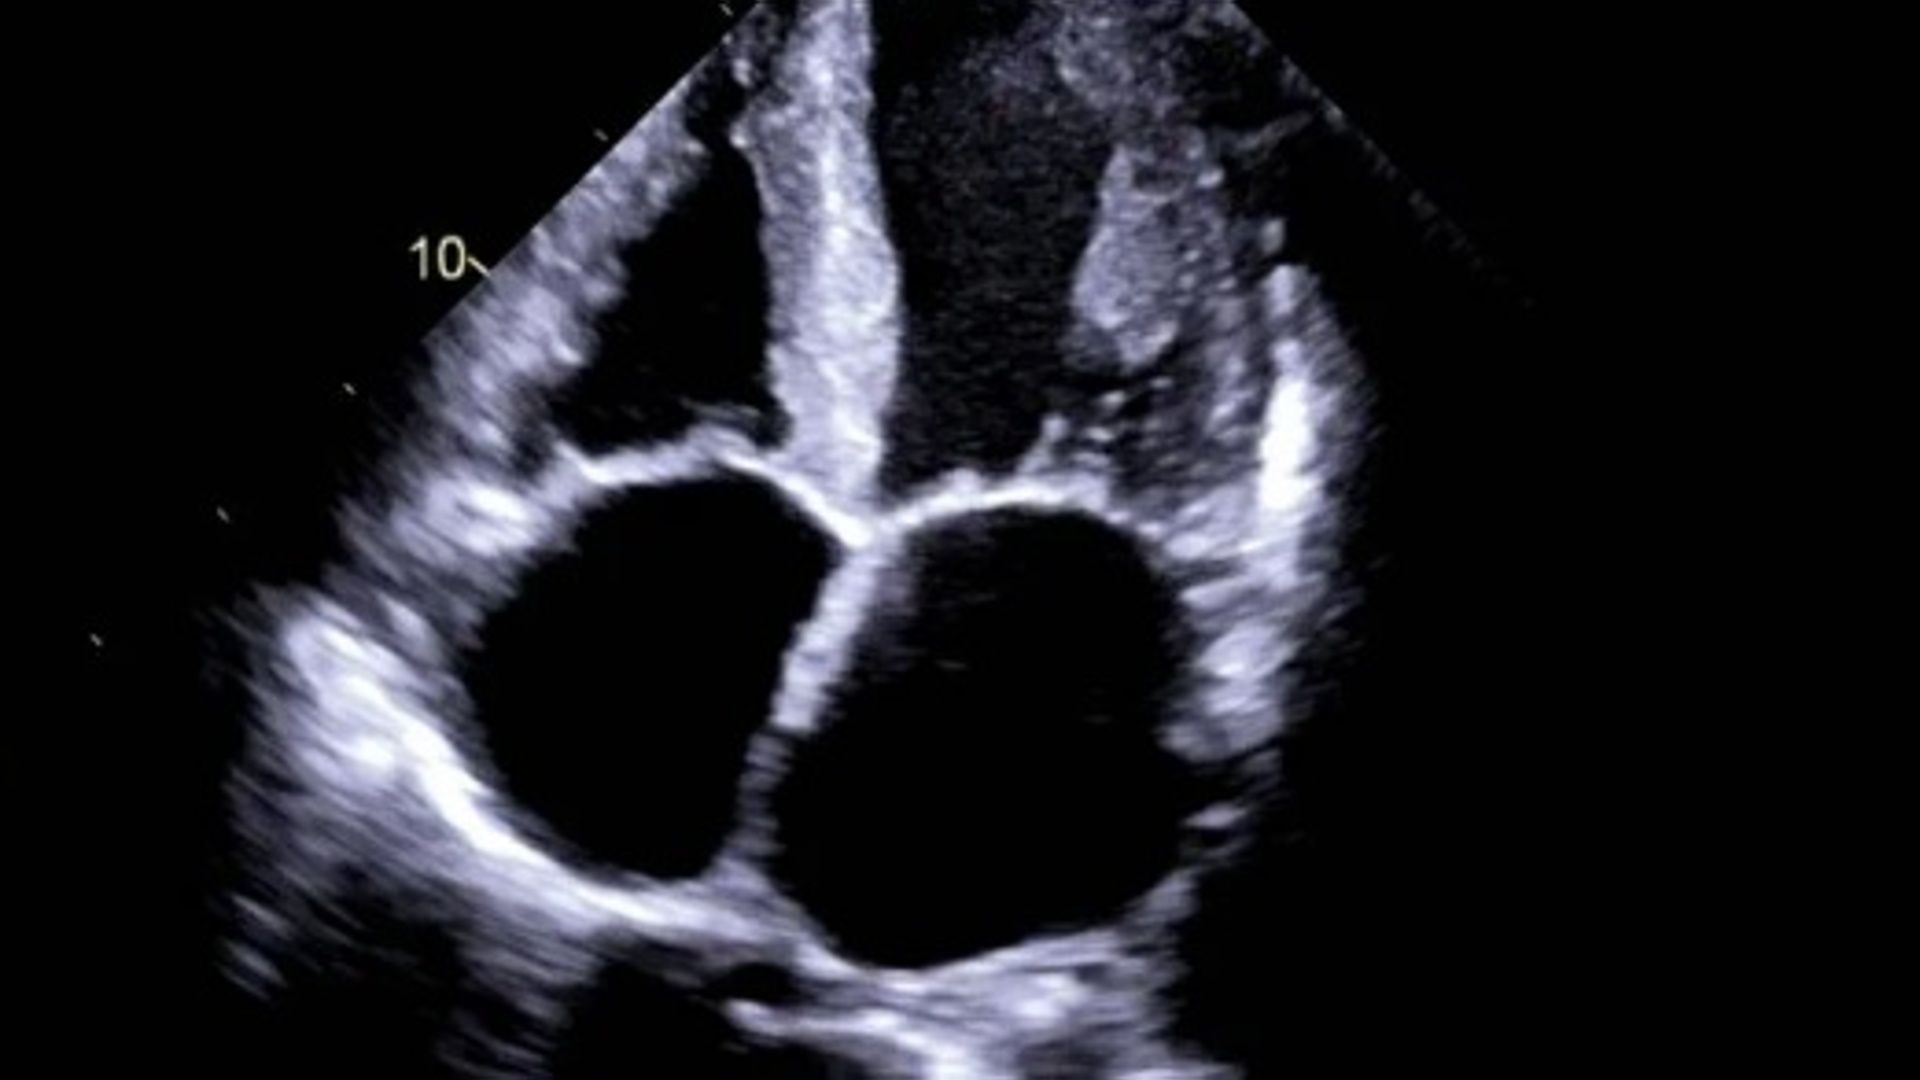

L’amiloidosi cardiaca è una patologia complessa e a lungo rimasta poco riconosciuta, perché i suoi sintomi iniziali – affaticamento, mancanza di respiro, gonfiore agli arti inferiori – sono comuni a molte forme di cardiopatia e spesso vengono attribuiti all’età o allo scompenso cardiaco «tradizionale». In questa malattia, il deposito anomalo di proteine nel muscolo cardiaco ne compromette progressivamente la capacità di rilassarsi e di pompare sangue in modo efficace. Il quadro clinico che ne deriva può sovrapporsi a quello delle forme più diffuse di scompenso cardiaco, rendendo la diagnosi particolarmente insidiosa. Per anni, proprio per questa somiglianza, l’amiloidosi cardiaca è stata considerata un vero e proprio «camaleonte clinico», spesso identificato solo in fase avanzata. Negli ultimi anni, tuttavia, lo scenario è cambiato in modo evidente. L’introduzione di tecniche di imaging cardiologico avanzato, insieme a percorsi diagnostici più strutturati e a una crescente formazione dei clinici, ha reso possibile riconoscere l’amiloidosi cardiaca con maggiore precisione e tempestività. Oggi non è più una diagnosi eccezionale, ma una condizione che viene considerata sempre più spesso nel percorso diagnostico di alcuni pazienti con scompenso cardiaco, in particolare nella popolazione anziana.